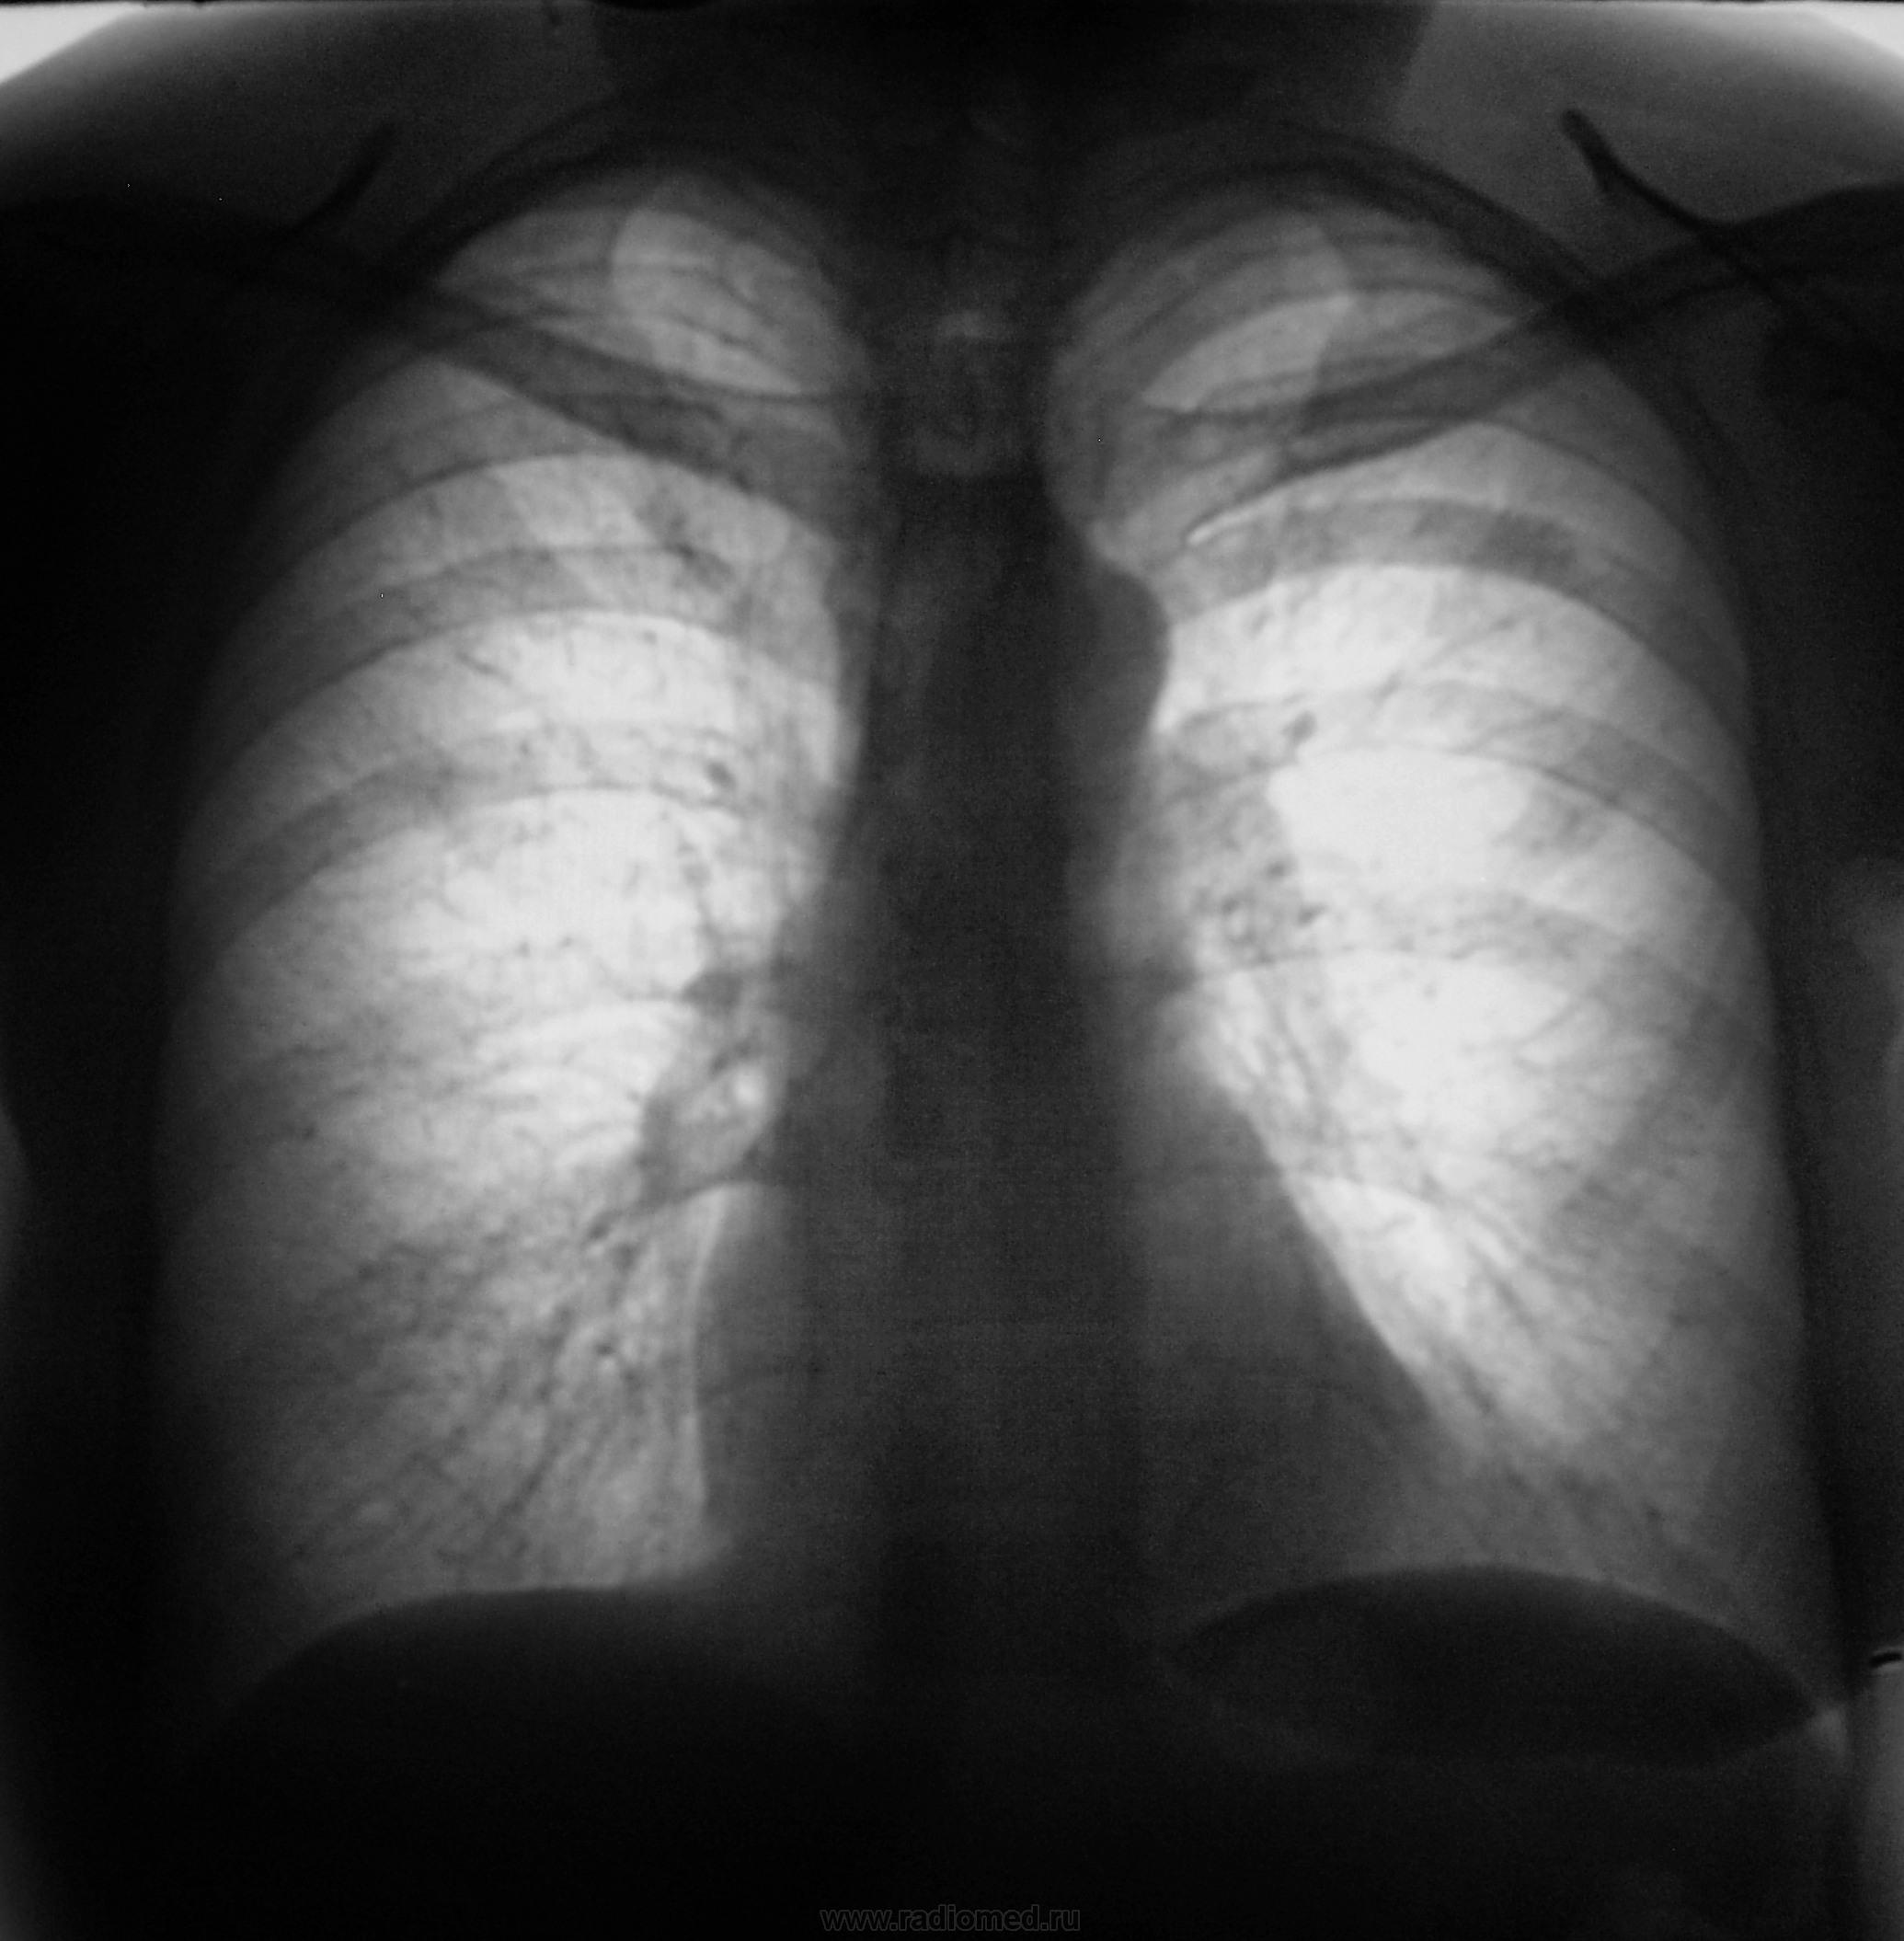

Произведены томограммы.

Первый срез.

Второй срез.

Третий срез.